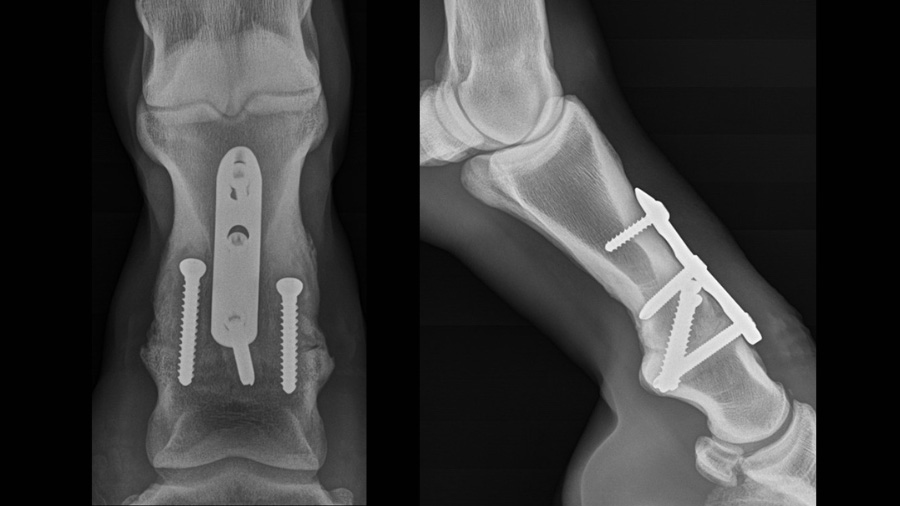

We continue to employ a unicortical screw in the H3 position as we have not encountered any negative consequences. One report has questioned the ability of a unicortical screw to effectively create compression when placed in the load position and argued that a bicortical screw is necessary for that purpose, otherwise toggling of the screw would occur mitigating the compressive effect of the screw. Although this could occur in bone with a very thin cortex or poor quality osteopenic bone, it would be readily apparent to the surgeon when the screw is tightened. The evidence for this occurring in PIP arthrodesis in a typical candidate for the procedure is debatable. The dorsal cortex of the mid-diaphysis of the proximal phalanx in the horse is of robust thickness and density and provides adequate working length for the screw to function as intended. In our experience, toggling of the screw and failure to provide compression has occurred in only one patient out of the multitude of patients treated in our hospital. This includes numerous patients less than a year old as well over 20 years old, many of which had chronic severe lameness and might be expected to have lower quality bone. Furthermore, when this argument was initially proposed, evaluation of the angle of unicortical screws before and after tightening among our clinical cases failed to demonstrate any evidence of toggling (Fig. 4).

However, in the rare instance it might occur, it would be readily apparent to the surgeon and easily remedied by replacing it with a bicortical screw.